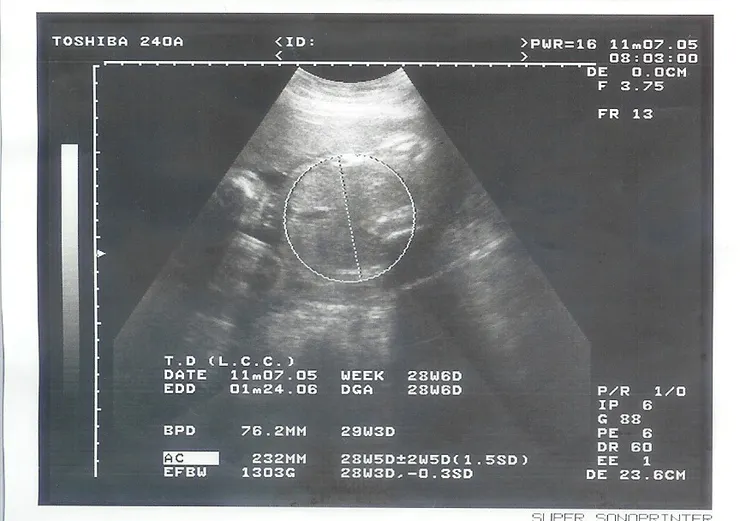

護士把超音波照撕給我,這次是小咪頭圍的照片。